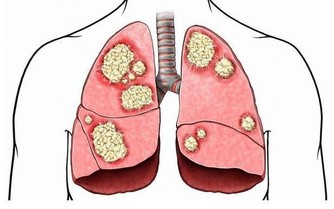

4、肺活量好

研究顯示,肺活量大小和身體各系統的機能、新陳代謝的能力等密切相關。肺活量就像我們的心臟活力,一旦下降內部機體能力也隨之下降。所以,若是人到了50歲之後,肺活量還很好,那恭喜你,屬於長壽體質。